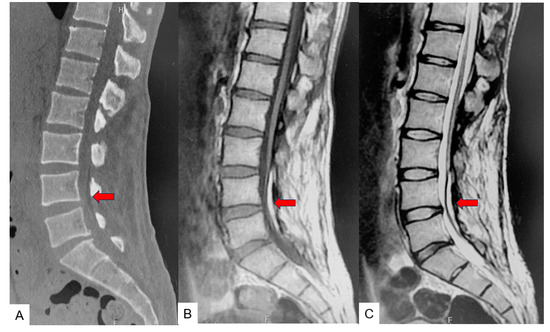

2.3. Preoperative Imaging

2.5. Postoperative Images